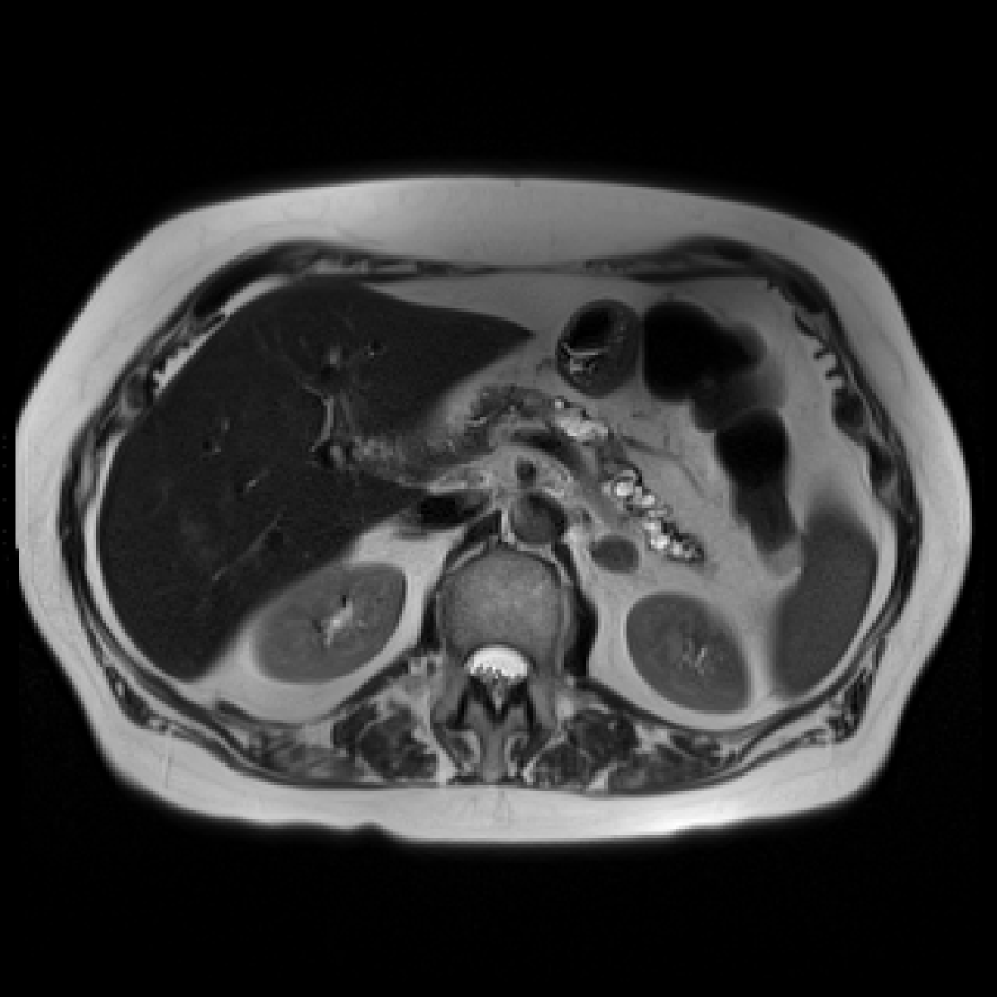

Accurate pancreas segmentation is a critical prerequisite for precise cyst analysis and classification. Recently, we developed PanSegNet [zhang2025large], a novel segmentation architecture incorporating linear self-attention layers [zhang2022dynamic] within the nnUNet framework [isensee2021nnu] to enhance global information modeling capabilities while maintaining computational efficiency (Fig. 1). PanSegNet demonstrated exceptional segmentation performance across both T1W and T2W modalities, achieving mean dice scores of 86.817.30% and 89.626.38%, respectively (Table 1, Fig. 2b-c). This performance significantly exceeded that of Swin-UNETR [hatamizadeh2021swin], one of the most used state-of-the-art transformer-based medical segmentation models, which achieved dice scores of 79.091.40% and 76.290.66% for T1W and T2W, respectively (). In this study, we integrated PanSegNet into our Cyst-X engine along with a classifier for risk prediction. In Section 2.2, we show that the choice of segmentation model affects the classification results. The performance advantage of PanSegNet was consistent across all seven medical centers, demonstrating robust generalization despite variations in imaging protocols and equipment (Table 1). This cross-institutional reliability is particularly important for clinical applications, where model performance must remain consistent regardless of imaging site or acquisition parameters.

Each patient was categorized into one of these three ground truth classes: no risk/control, IPMN low-risk, or IPMN high-risk. To evaluate variability in image acquisition, we applied uniform manifold approximation and projection (UMAP) to image quality indicators, revealing distinct clustering patterns by imaging center and slice thickness. This heterogeneity reflects real-world clinical variability, enhancing the dataset’s generalizability while presenting technical challenges for model development. Fig. 6 shows examples of low-grade, high-grade, and cancer developing IPMNs from the Cyst-X dataset.